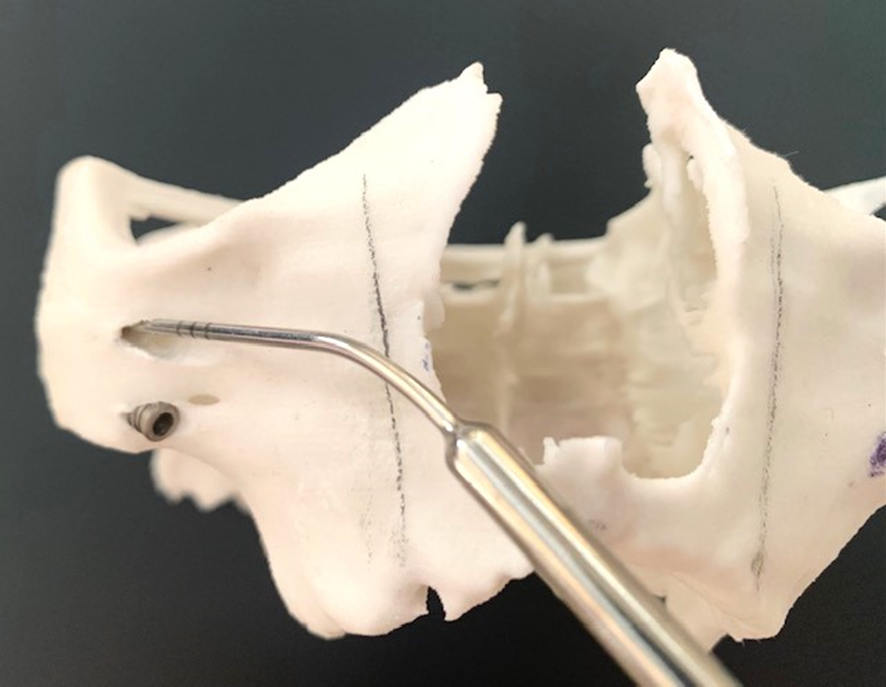

A montagem do Pilar Z exige do cirurgião-dentista habilidade e curva de aprendizado. Nem sempre se consegue adaptar o Pilar Z sem interferências ósseas. Por essa razão, adotamos uma rotina de instalação dos pilares na prototipagem, simulando assim, uma situação muito próxima do real no procedimento cirúrgico.

Desta forma, pode-se observar possíveis contatos ósseos no corpo da maxila ou do zigoma que não permitam o assentamento passivo do Pilar Z.

Conseguimos orientar a plataforma do Pilar Z através da chave de alinhamento, para assentamento passivo da prótese. A visualização do local de emersão do Pilar Z junto ao rebordo alveolar nos indicará onde realizar a osteotomia para confeccionar o “nicho” que abrigará a plataforma do mesmo.